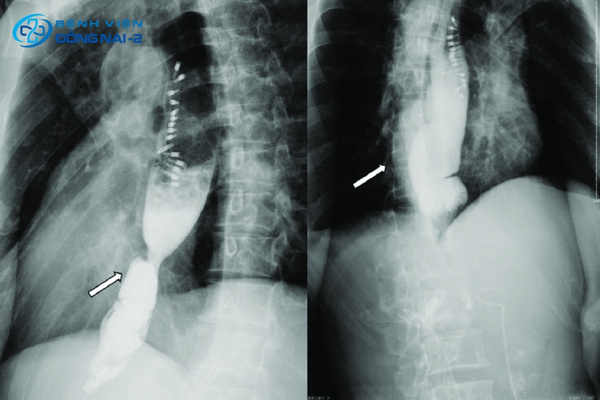

Chụp X-quang của hệ thống tiêu hóa trên

Chụp X-quang đường tiêu hóa trên với dung dịch bari giúp hiển thị rõ hình ảnh thực quản và dạ dày